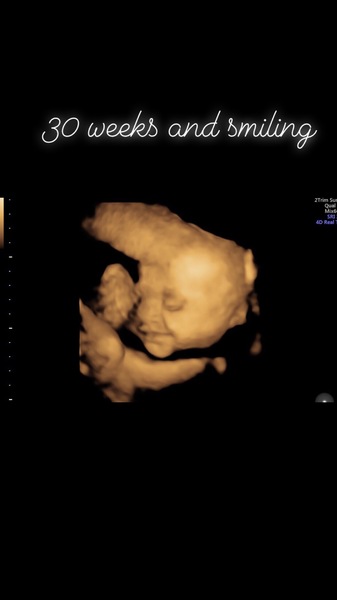

I’ve got a 4d scan booked at the end of the month which is exciting, I feel more relaxed at those private ones as I don’t have the hospital anxiety and flashbacks. Would deffo recommend them to anyone! Wanted Oh to see him and we had a lovely one with Lily last time, I’ve popped the picture on of Lily’s scan, it’s one of my favourite pics of all time as it was the only time I got to see her smile, means so much to me now xxxx

@Anon20something such a beautiful picture... We were hoping to get a 4d scan booked but think I'm to far along for it now... The ones around here suggest up to 28 weeks x

@Anon20something that's a beautiful scan of Lily and such a lovely thing to have and keep.

What a lovely picture @Anon20something, she really does look like she is smiling!

@Anon20something what a precious picture that is. X

@Anon20something such a gorgeous photo, she looks so beautiful xx

@Anon20something That is a beautiful picture of Lily!!

@Anon20something beautiful picture 💖